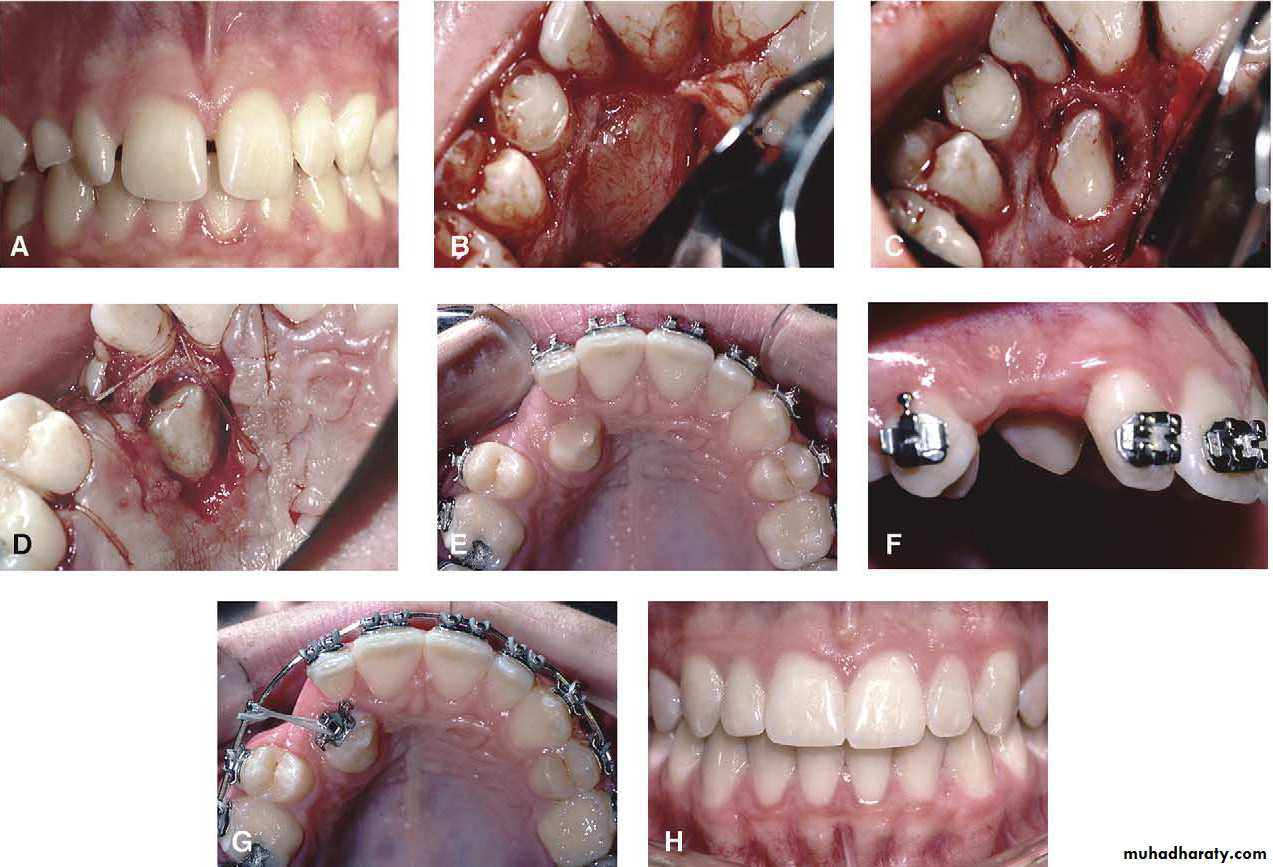

Surgical exposure :the path of eruption is not obstructed

impaction

Surgical exposure with orthodontic traction: the path of eruption is obstructed

Surgical exposure with orthodontic treatment (palatal approach )